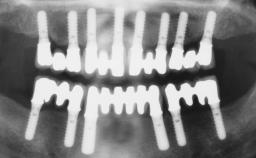

Conventional Loading of Six Implants in the Mandible and Final Restoration with a Full-Arch Metal-Ceramic FDP

# of Implants 6

Type of Implants One-Piece

Defining Characteristics Fully edentulous lower jaw to be rehabilitated with two or more implants

Modality > 4 implants, extending to mental nerve region

Bone Volume Horizontally and vertically sufficient

Retention Screw-retained, with 4 or more splinted implants Screw-retained, with 4 or more splinted implants